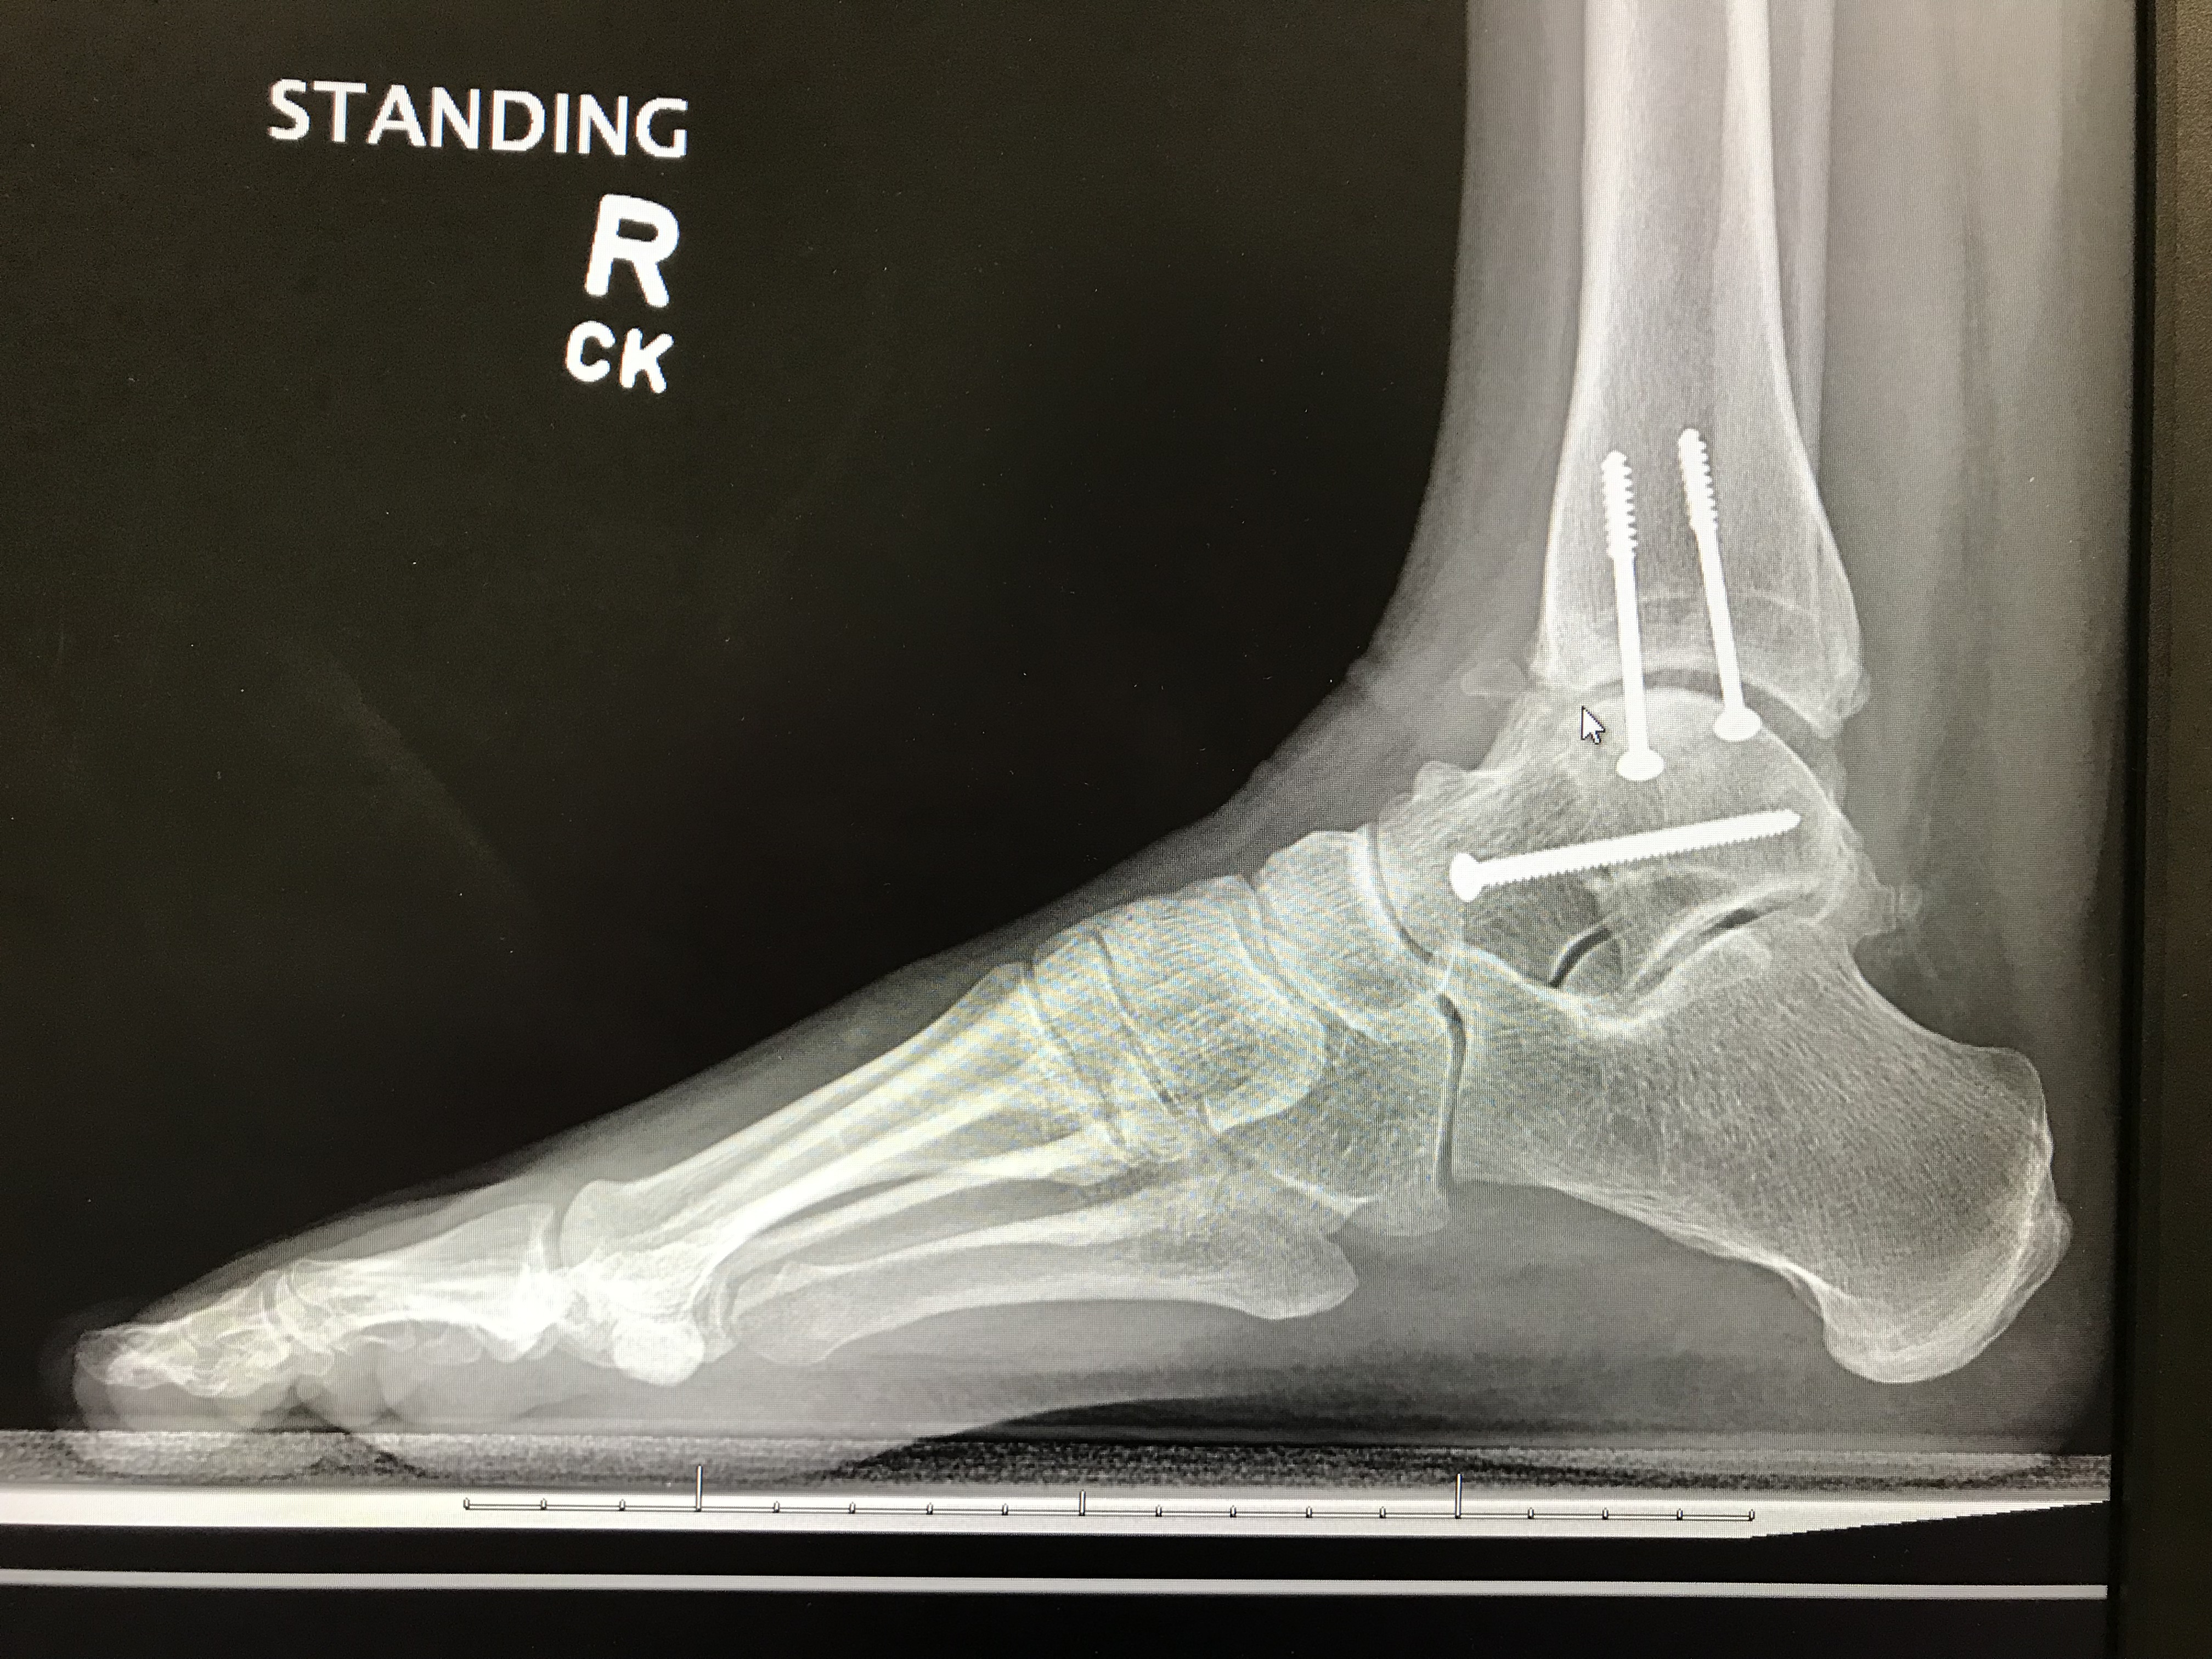

Anyone who knows me knows about the accident, but what a lot of people don’t know (and don’t really understand unless they too have chronic pain) is that I deal with pain on a daily basis because of it. In fact, more days than not, I walk around with a stabbing pain in at least one area of my ankle. My latest X-rays show that it is, in fact, riddled with arthritis and there is almost no cartilage left between the joint. Which means bone hits bone with every step I take and any hope of gaining back full range of motion is pretty much non existent.

And for any of my friends in the medical field that are curious, I am attaching my X-rays. They fascinate me, but I might be the only one. It’s a little hard to get a clear view since I took this picture from the computer screen they pulled them up on (my front view pictures didn’t turn out well), but I think you can see that there isn’t much space between the front of the joint where cartilage should be, and you can also see how messy the lines in the joint are when they should be clean. There’s also a little ball of arthritis hanging out in the front there close to where the mouse is pointing.